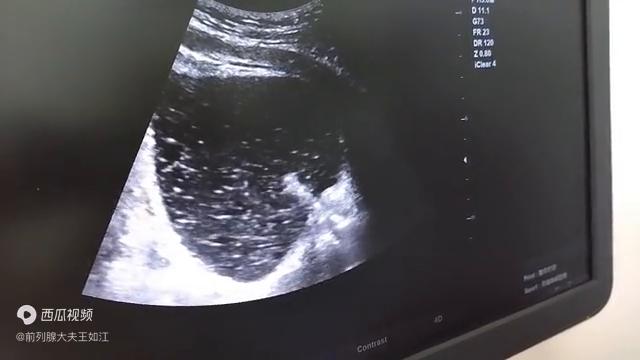

今天根据b超图像来让大家看一看,给大家讲一讲什么是尿道疏通扩张术。尿道扩张疏通术是积善堂,巧妙地利用导尿管和导尿管头上的水囊,巧妙地利用医疗器械,来对尿道里面的钙化灶,或者是对包绕卡压。

尿道内口的钙化灶,进行疏通和扩张的一种简便,但效果立竿见影的疗法。大家可以看图,一般做尿道疏通是选择在做钙化消融术至少在一周以上。它的前提是钙化灶必须首先被消融变得松软,这是它一个基础条件,变得松软。有很多钙化灶就最后分泌到了包绕尿道的叫黏膜下腺体。